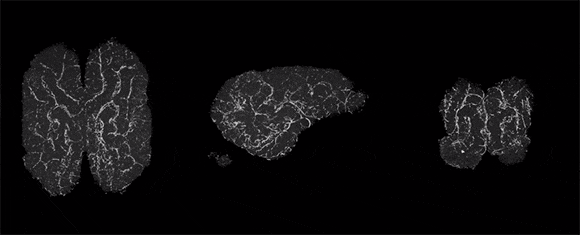

実験では、食肉用のブタ32頭から摘出した死後4時間経過した脳をBrainExに装着。6時間ほど保護液のかん流を行うと、未処理の脳と比べてはっきりとした違いが生じた。

組織と細胞の構造が維持されており、細胞死が抑制されていることが確認されたのだ。

この画像を大きなサイズで見るさらにグリア細胞と血管が刺激に反応したり、代謝にあわせて自発的なシナプス活動が見られるなど、一部の分子機能と細胞機能が復活までしていたのである。